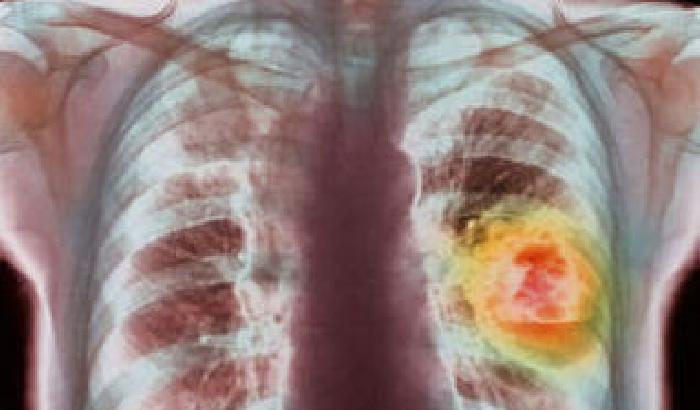

Il fumo passivo provoca il cancro, anche se un italiano su otto fa finta di ignorarlo. È il risultato di una ricerca condotta dall’Aiom, l’Associazione italiana di oncologia medica. E di cancro al polmone si muore: 38 mila le diagnosi ogni anno e 34 mila i decessi nel 2013. Per colmare questo gap d’informazioni Aiom con i patrocinio delle associazioni Insieme per il cancro e Walce (Women against lung cancer Europe) e il sostegno della casa farmaceutica Boehringer Ingelheim lancia una nuova campagna d’informazione, destinata ad evitare che le nuove generazioni fumino. La campagna si concretizza in tre brochure informative sui rischi del fumo e sulle cure possibili per il cancro ai polmoni. “La legge Sirchia, che ha vietato di fumare nei locali, ha fatto effetto ma ora non dobbiamo mollare la presa”, spiega il presidente eletto di Aiom Carmine Pinto. Il fenomeno non può essere sottostimato: in Italia i fumatori passivi sono 15 milioni, il 26,5% della popolazione e la metà degli under 14 ha in casa un tabagista. A questo si aggiungono 150-300 mila polmoniti e bronchiti nei bambini al di sotto dei 18 mesi.

L’ignoranza sugli effetti del fumo passivo nell’incidenza dei tumori (in due casi su dieci i pazienti sono fumatori passivi) provoca un altra distorsione della realtà: l’eccessivo stigma del fumatore malato, considerato “uno che se l’è cercata”. Al contrario, visto che la malattia è curabile seppur con difficoltà (anche se un italiano su due pensa erroneamente l’opposto), questa sfiducia nelle possibilità del paziente e imputargli le colpe della sua malattia sono due condizioni che non aiutano la cura. (lb)